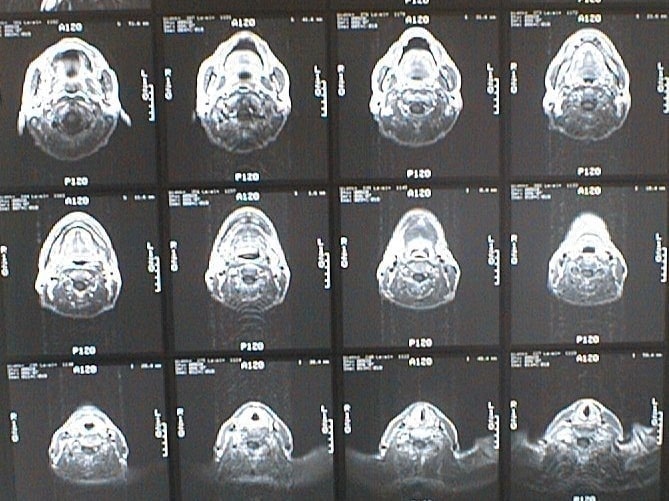

末期がん宣告時と末期がん消滅時の診断画像比較

ここでは、末期がんと宣告された時のCT&MRI画像と、その約3か月後の末期がん消滅時の画像を比較して頂けます。(写真左が「末期がん宣告時の画像」、写真右が「末期がん消滅後の画像」)

MRI画像比較

中咽頭末期がんMRI画像①

入院当時MRI画像①

中咽頭末期がん消滅時MRI画像①

入院3か月後癌消滅MRI画像①